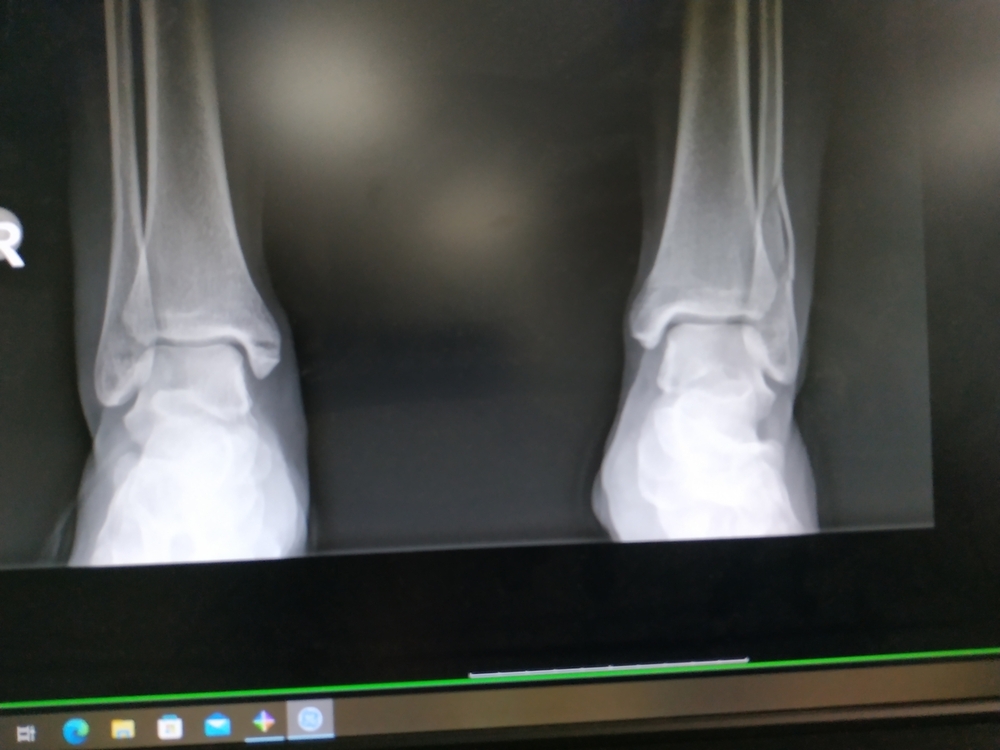

Kurczę a te szyny gipsowe robią mi się coraz luźniejsze. Czy w przypadku kości strzałkowej takie całkowite, idealne unieruchomienie jest istotne ?

IMG_20220119_151518.jpg

Jest istotne. Po ustąpieniu obrzęku szyna gipsowa powinna być zastąpiona pełnym gipsem lub dla wygody opatrunkiem syntetycznym ale pełnym, okrężnym. Złamanie dobre. Dobrze się zrasta. Pierwszy zrost bez przebudowy szpary złamania to ok. 6 tyg. Pełny zrost 12 tyg. 100% przebudowy złamania - rok.